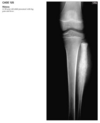

Anteroposterior view of the pelvis

shows diffuse,

uniform, bony sclerosis and a subtrochanteric frac-

ture of the proximal left femur.

A lateral chest ra-

diograph shows the

sandwich appearance of the vertebral bodies caused

by increased sclerosis of the superior and inferior

end plates.

Radiographs of the knees show splaying of the metaphyses and alternating radiolucent bands in the distal

femurs and proximal tibias and fibulas bilaterally. (Erlenmyer flask)

Diagnosis: Osteopetrosis

Defect in osteoclastic resorption.

Precocious (AR Lethal) and Delayed (AD asymptomatic)

Generalized osteosclerosis and diffuse cortical thick-

ening with narrowing of the medullary cavity.